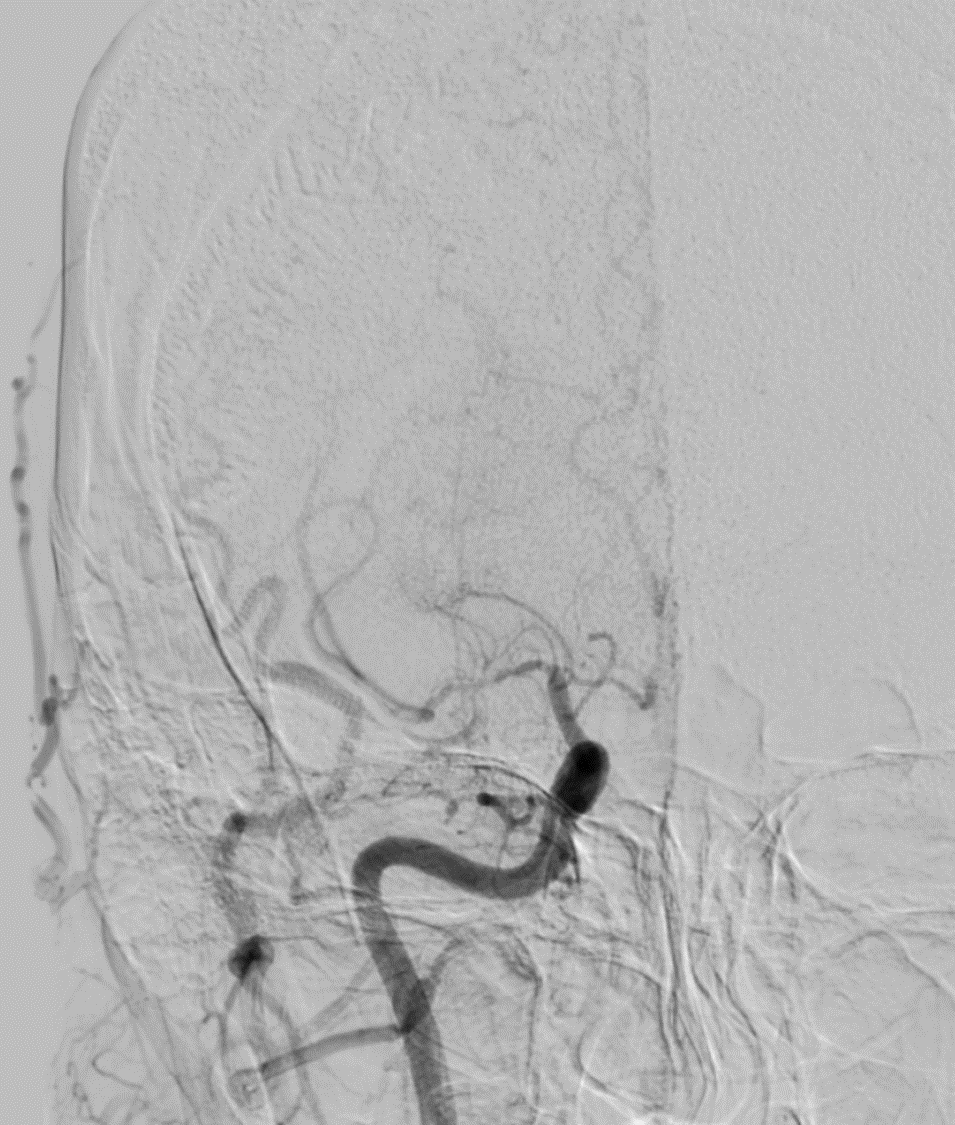

DSA also confirmed the extensive clot. In view of her recent LSCS 20 days ago, we were hesitant about giving IV lytics (urokinase infusion). Hence went in with an ACE 5 Max catheter and sucked out a mountain of clot